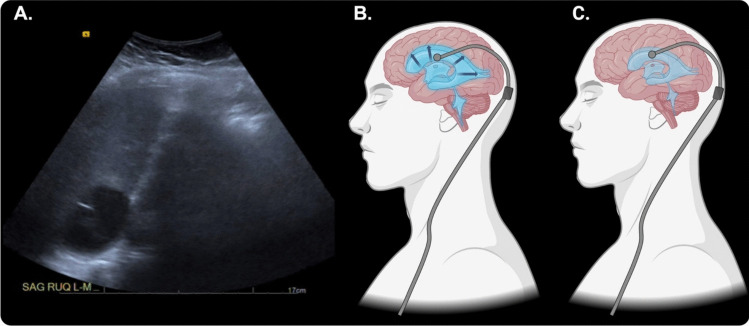

Abstract Image